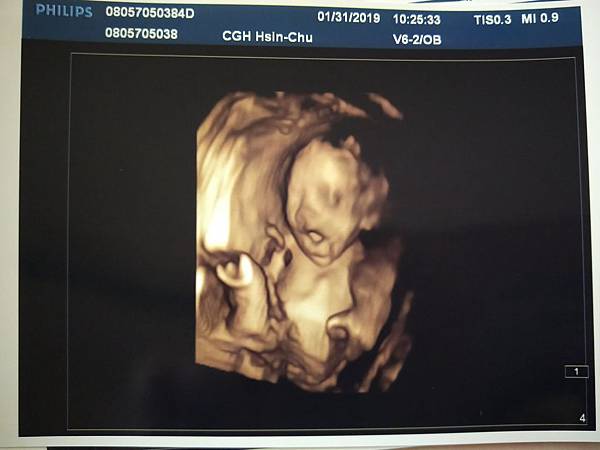

2019.01.15(二)高層次檢查

預約時間是10:50,不過實際檢查大概已經11:20